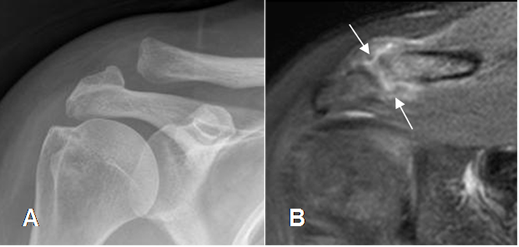

Fig 54. Esguince de articulación acromioclavicular.

A: Rx AP. Aumento y desalineación de la articulación acromioclavicular.

B: RM coronal en STIR. Hiperintensidad y ruptura de los ligamentos acromioclaviculares, por esguince G III.